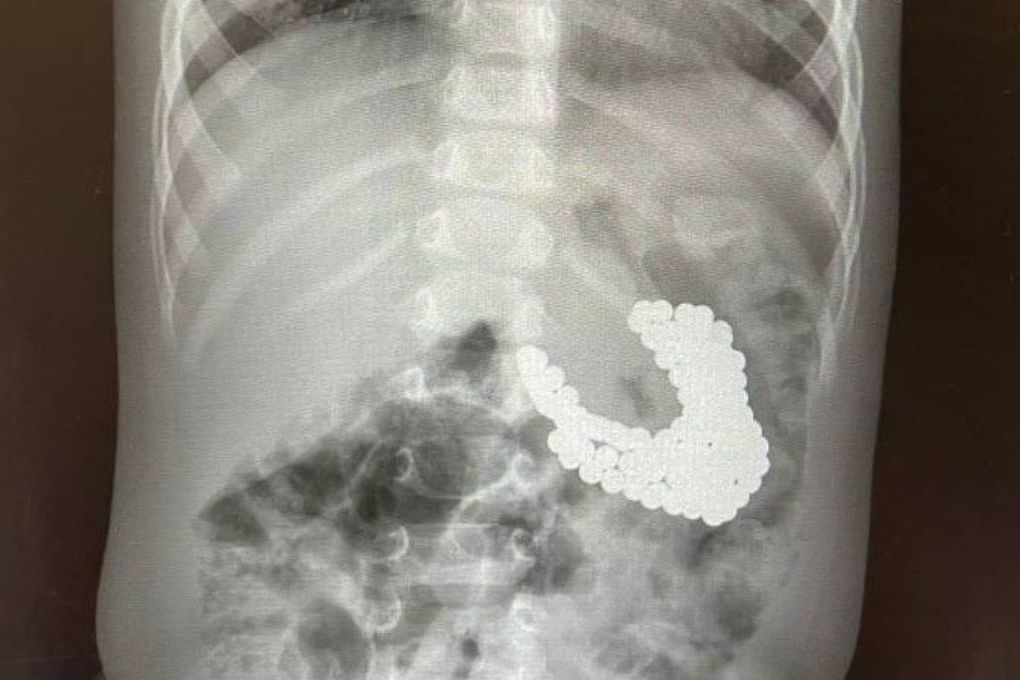

Ребенок съел вату

Ребенок съел вату 105 фото